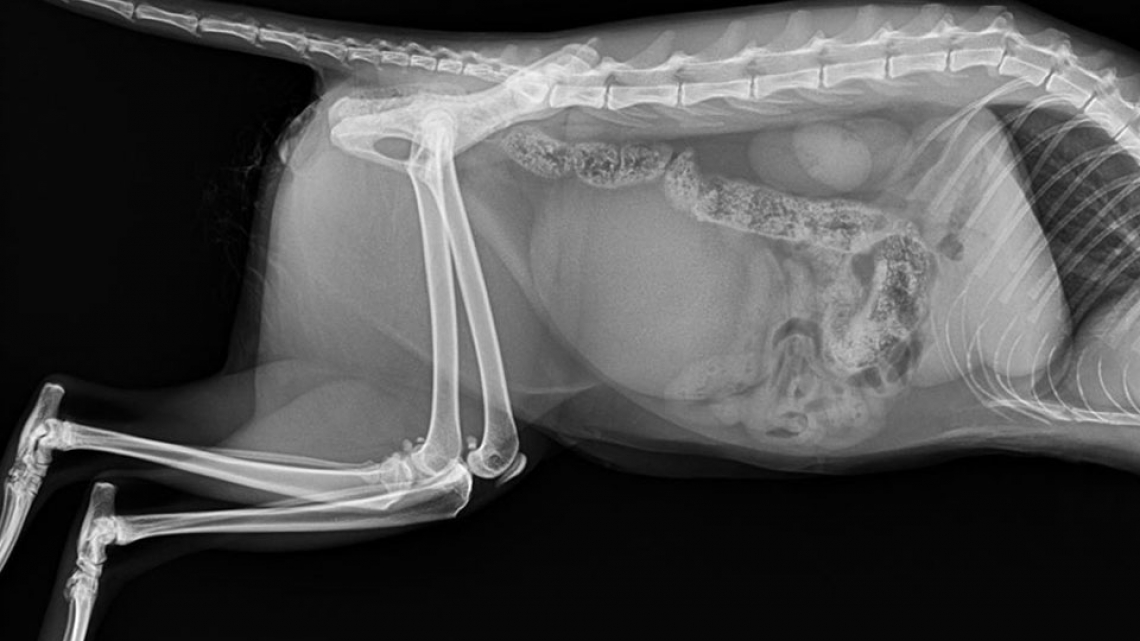

Mini SOP-LC (for 2,0mm srews) were used for stabilisation of vertebral luxation and fracture in cat.